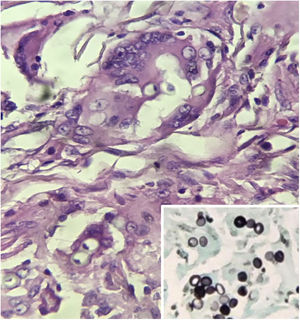

A biopsy of the lesion was performed and histopathology revealed a nodular granulomatous inflammatory infiltrate involving the entire dermis and hypodermis, consisting of epithelioid histiocytes and numerous giant cells, containing rounded fungal structures in a catenulate arrangement compatible with Lacazia loboi (Figs. 2 and 3).